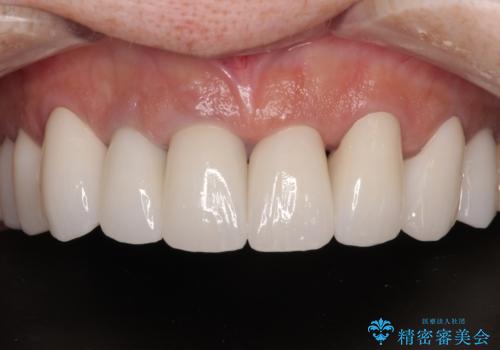

20年以上前から、むし歯になったり詰め物が欠けたりする度に部分的に処置を行ってきたそうですが、この際統一感のある前歯にしたいとのことで、上顎前歯9本をオールセラミッククラウンによる補綴治療を行うこととしました。

色調が統一されるだけでなく、歯肉ラインに見えていた茶色の境目も綺麗に改善されました。